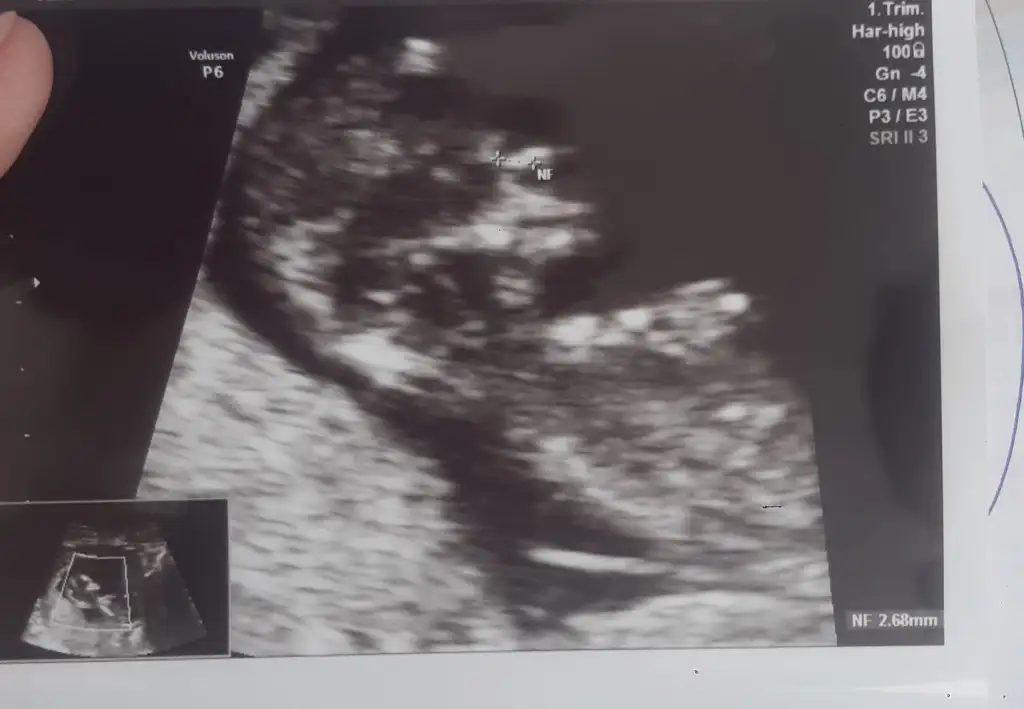

Merhabaa, bana da bakabilir misiniz? Karından bakıldı

Eklentiler

• 0D595629-7DC9-4FD7-BB9A-F66E3E08C51E.webp

0D595629-7DC9-4FD7-BB9A-F66E3E08C51E.webp

20,9 KB · Görüntüleme: 76

• C605FB47-24E8-406F-969A-7351DA55E08B.webp

C605FB47-24E8-406F-969A-7351DA55E08B.webp

18,5 KB · Görüntüleme: 78